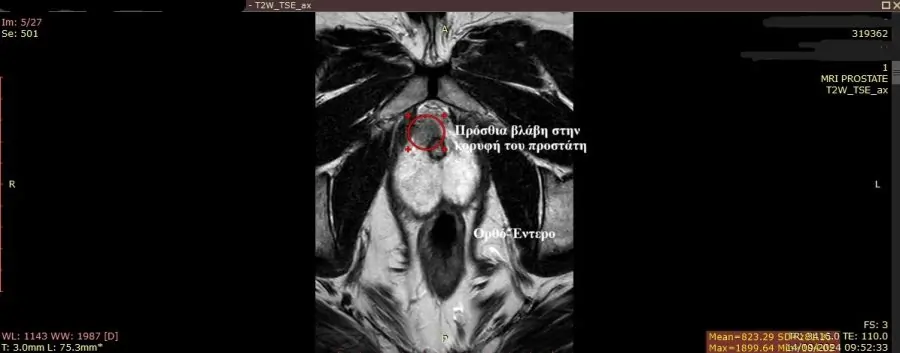

Ακριβώς λόγω της πρόσβασης μέσω του περινέου (η περιοχή μεταξύ όρχεων και πρωκτού) η διαπερινεϊκή βιοψία υπερέχει σημαντικά της διορθικής καθώς η πρόσβαση σε ανατομικά δύσκολες περιοχές στον προστάτη είναι απλή και εύκολη ενώ στην διορθική σε πολλές περιπτώσεις μη εφικτή.Η πρόσθια ζώνη, η μεταβατική ζώνη και ο μέσος λοβός είναι ανατομικά απομακρυσμένες θέσεις που η διορθική βιοψία από το έντερο έχει αντικειμενική δυσκολία στο να τις προσεγγίσει με αποτέλεσμα οι βιοψίες σε ασθενείς που έχουν ύποπτες περιοχές σε αυτές τις θέσεις να είναι μειωμένης διαγνωστικής ακρίβειας καθώς πολλές φορές δεν μπορούν καν να ληφθούν δείγματα από αυτές(Εικόνα 3).Στην διαπερινεϊκή αντίθετα βιοψία προστάτη η ανατομική εγγύτητα του περινέου με τον προστάτη και η παράλληλη λήψη των δειγμάτων καθιστά απλή και αποτελεσματική την λήψη δειγμάτων από τον προστάτη ακόμα και αν οι υποπτες περιοχές βρίσκονται στην πρόσθια ζώνη, στην μεταβατική ζώνη και τον μέσο λοβό, καθιστώντας την διαπερινεϊκή fusion βιοψία προστάτη εξαιρετικά αποτελεσματική με διαγνωστική ακρίβεια που υπερβαίνει το 95%.

Εικόνα 3.Χαρακτηστική βλάβη στην πρόσθια ζώνη του προστάτη όπου η βλάβη όπως απεικονίζεται βρίσκεται μακριά από το ορθό έντερο καθιστώντας δύσκολη την λήψη της κατά την διορθική βιοψία εντέρου.